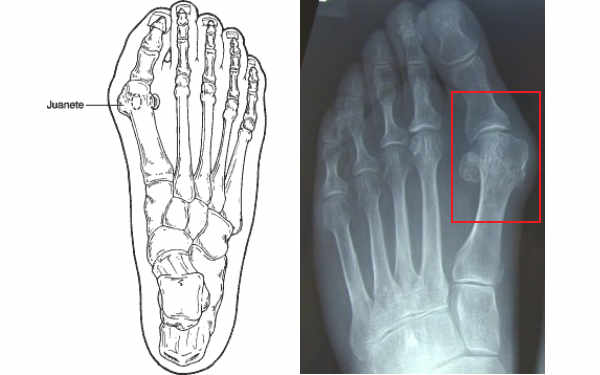

Hallux Abductus Valgus (Juanetes)

El hallux valgus, también llamado “juanete”, es uno de los problemas más comunes del ante pie que puede causar dolor, deformidad y disminución de la movilidad. Son múltiples los factores que influyen en el desarrollo y progreso de la patología, ya sean intrínsecos y/o extrínsecos.

Esta patología se produce en la primera articulación metatarso falángica y cursa con una desviación del primer dedo hacia los otros dedos deformándolos secundariamente, además se produce un crecimiento de una prominencia ósea en la cabeza del primer metatarsiano llamada bunion.